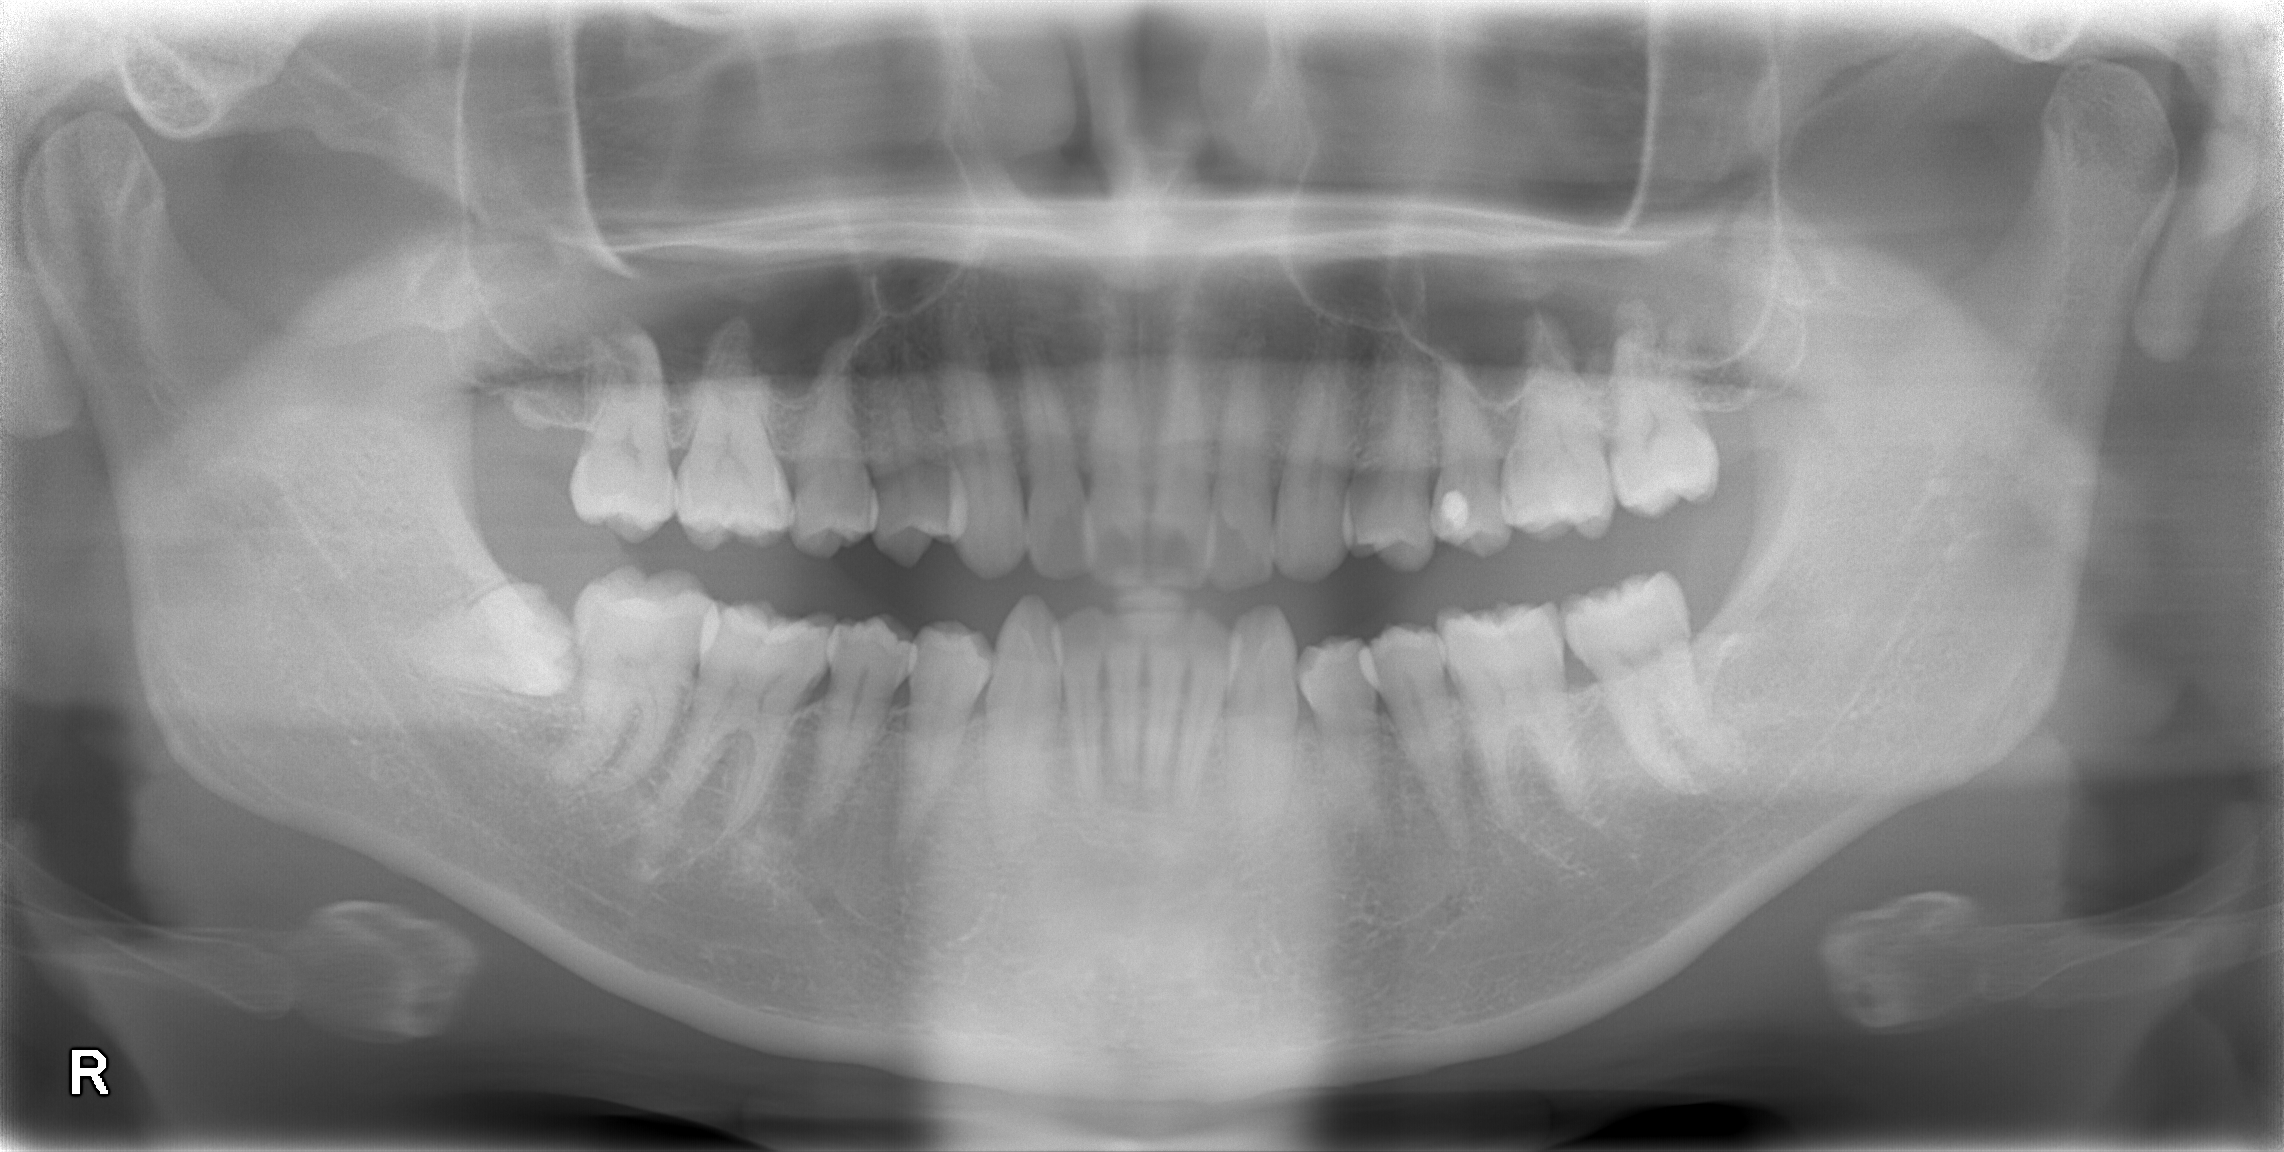

歯茎の下にほぼ全て埋まった親知らずの抜歯